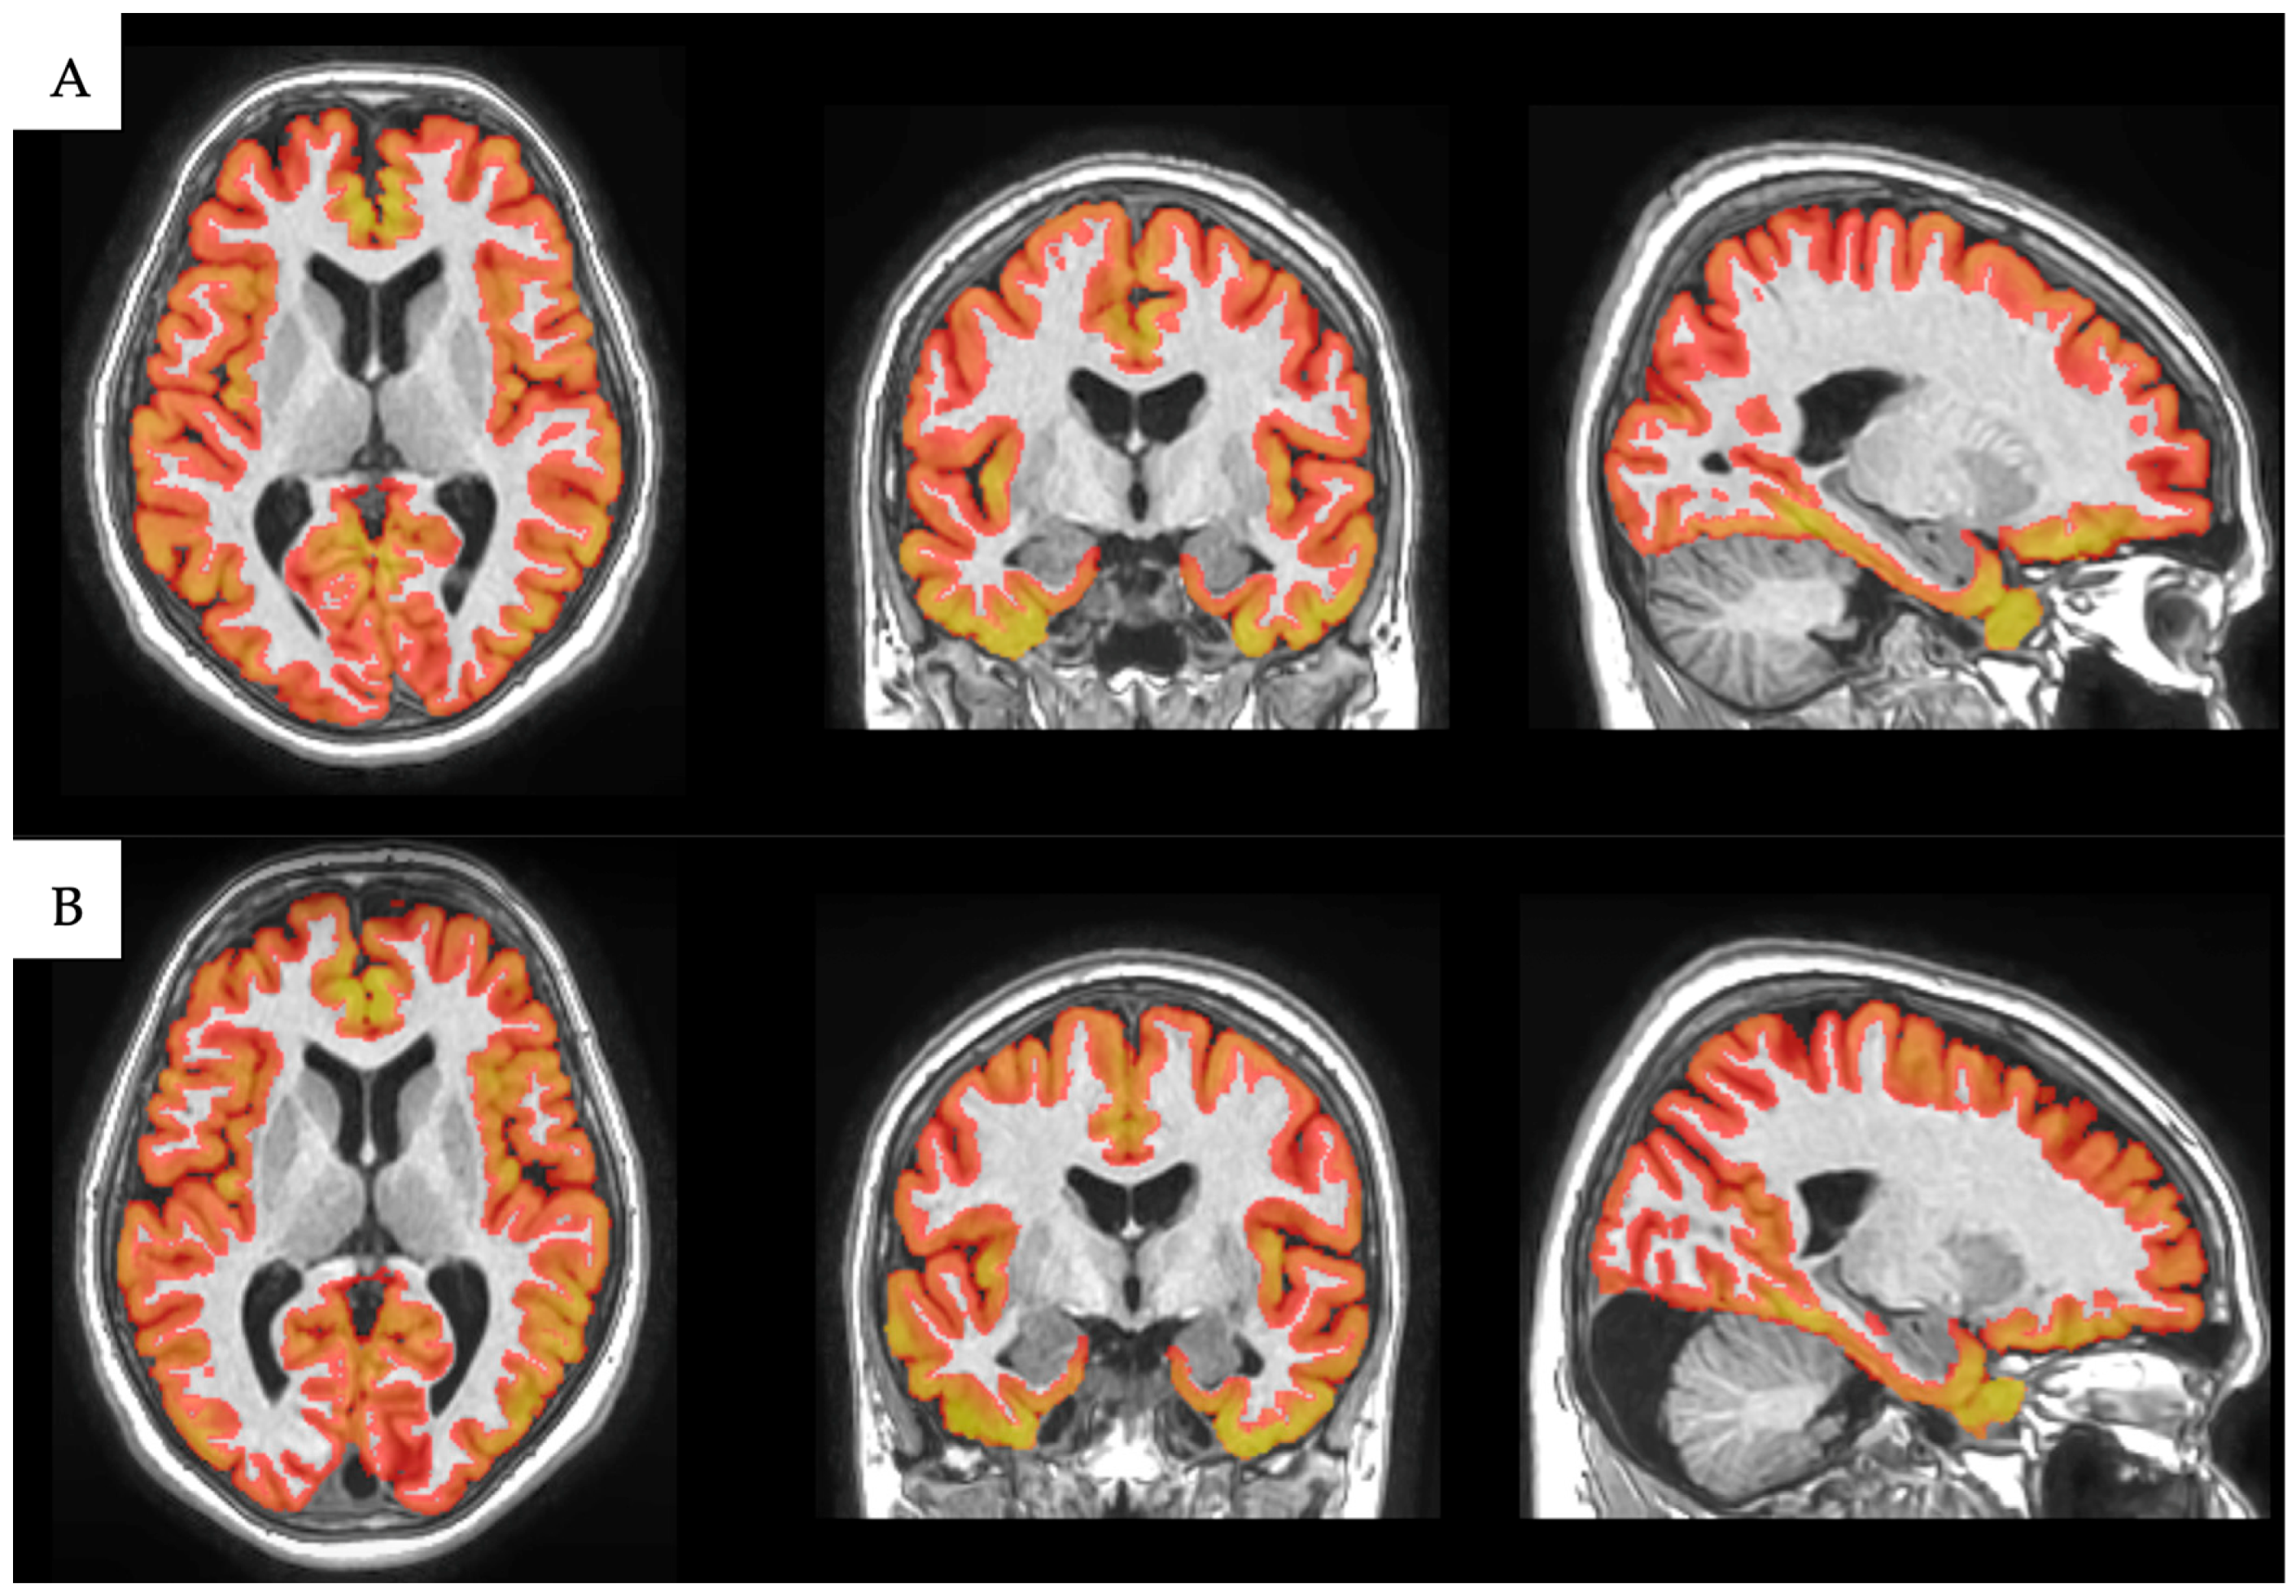

2.3. Image Processing

Volumetric Analysis with volBrain